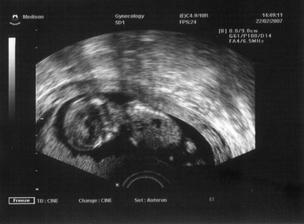

Jelikož se sen proměnil ve skutečnost, tak k nám přiletí čáp nebo vrána koncem velkých prázdnin 2007. Už jsem začali nakupovat, většinu věciček pro mimi kupuji v sekáči,jelikož se domnívám, že je úplná škoda utrácet penízky za nové oblečení,které je nekřesťansky drahé.Miminko stejně nic neunosí a ze všeho za chvíli vyroste.Takže si fakt vybírám a zatím se mi daří...Moc se těšíme...